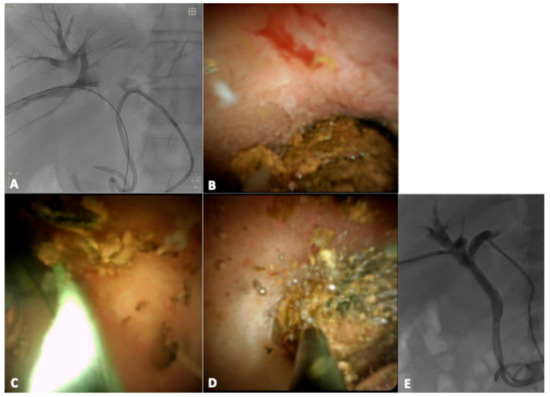

3. Results